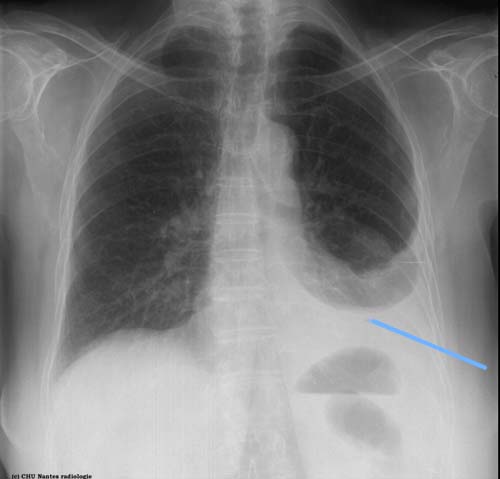

opacité basale gauche effaçant la coupole diaphragmatique et le cul de sac costo-diaphragmatique externe à limite supérieure arciforme , concave en haut et en dedans : épanchement pleural gauche